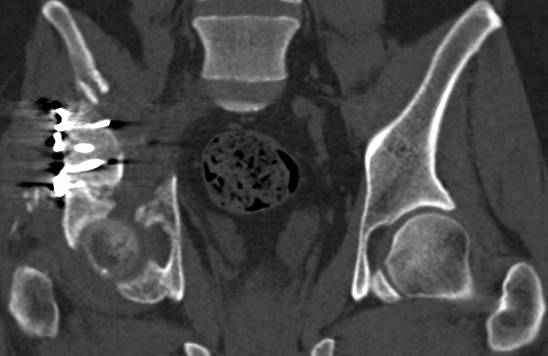

высылаю дополнительно сканы.

итак, второй вариант: высокий двухколонный с вовлечением КПС... Ни одно из основных повреждений не репонировано, кроме задней стенки. Скорее всего попытка реконструкции вертлуги сейчас будет очень травматичной и не очень эфективной, т.е. вероятный риск более значим, чем ожидаемая польза... Лучше подождать, и потом сразу эндопротез